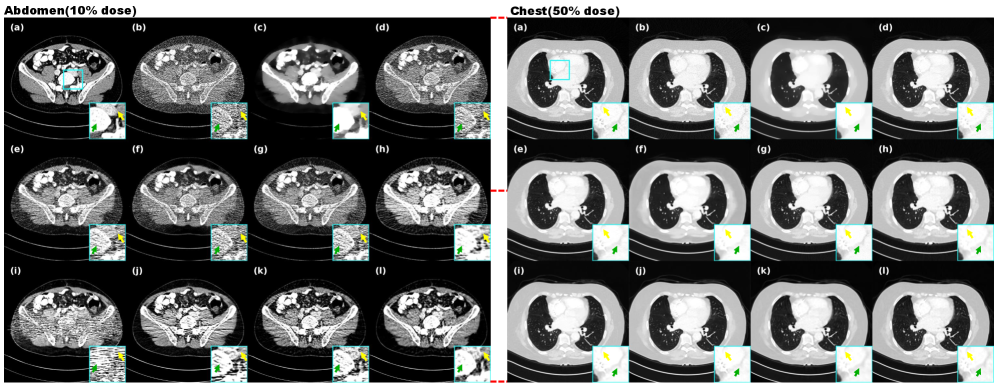

4.4.1 Evaluation of different datasets

This study quantitatively validates the model’s superiority using dose data from the Mayo and LIDC-IDRI datasets. Comparative experiments against traditional methods, self-supervised approaches, and clean-data-based iterative diffusion methods demonstrate the advancement of our approach from multiple perspectives, as clearly shown in Fig. 6 through transverse images, coronal images, sagittal images, zoomed regions, and residual maps. While traditional TV regularization achieves noise removal, it causes over-smoothing and compromises pathological features, with parameter sensitivity across different scanning conditions. Deep learning-based B2U suffers performance degradation due to limited adaptability to structured CT noise. Noiser2Noise introduces excessive randomness by adding artificial noise, leading to texture loss similar to TV methods. Prompt-SID, despite incorporating diffusion models and cue learning, shows limited effectiveness on the Mayo dataset. NBR, lacking our similarity enhancement strategy, produces less distinct lesion visualization in both lung and abdominal scans, as evidenced in Fig. 6 and Fig. 7.

As can be seen from Table 1, Noise2Sim, AdaReNet, and IPDM all showed good results, but Noise2Sim’s method based on batch data similarity requires higher data z-axis orientation, which resulted in a significant drop in metrics across different datasets, and the overly randomized selection of similar data can easily lead to drifting of CT values as shown in Figs. 6 and 8. However, our method mitigates the CT value mismatch due to the pixel-level weighted correction that achieves a balance in suppressing noise and preserving details. Notably, although the effect on the LIDC data is lower than that of AdaReNet, it requires independent noisy data with the same information, which cannot be strictly classified as self-supervised, and as shown in Fig. 8, the image produces a smoothing of the details on the muscle tissues and bones, which can interfere with the diagnostic performance of the radiologist to a large extent.

Our method best matches the reference in intensity variation, as shown in the line profile in Fig. 6, demonstrating superior reconstruction robustness. Crucially, our approach operates solely on single LDCT projection during both training and inference, offering a truly self-supervised solution suitable for label-scarce clinical environments.